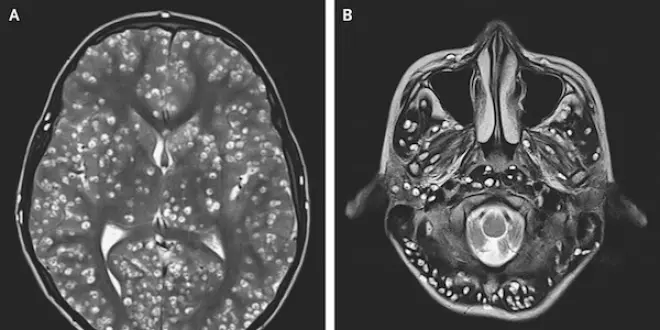

Une IRM cérébrale révèle de nombreuses lésions kystiques dans tout le cortex cérébral (photographie A) ainsi que dans le tronc cérébral et le cervelet (photographie B). Suite à cela, une écographie est réalisée et met en évidence ces mêmes kystes dans l'oeil et le testicule droit du patient. Le diagnostic est sans appel. Le jeune homme souffre d’une neurocysticercoce.

Chacune des tâches blanches ci-dessus est un kyste créé par les larves de Taenia solium. Mais, en raison d'une "forte charge kystique", aucun médicament antiparasitaire n'a pu été adminisitré. Cela aurait pu aggraver "l'inflammation et l'oedème cérébral", et provoquer "une perte de vision", indiquent les docteurs Nishanth Dev et S. Zafar Abbas, auteurs de l'article. Le jeune homme a donc reçu des médicaments antiépileptiques ainsi qu'un anti-inflammatoire, le dexaméthasone. En dépit cela, le patient est décédé deux semaines plus tard.